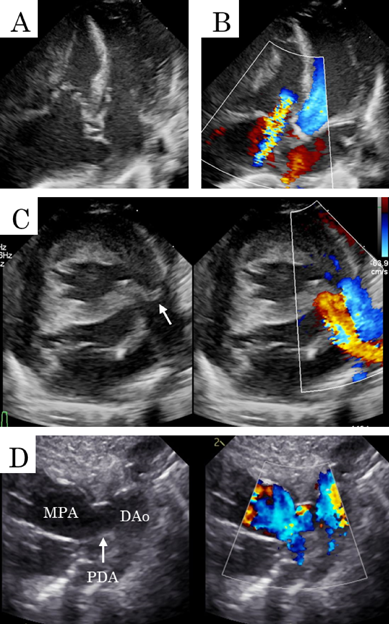

在胎35週の心室中隔欠損を伴わない肺動脈閉鎖における両側肺動脈絞扼術を用いた肺血流制御Bilateral Pulmonary Artery Banding to Regulate Excessive Pulmonary Blood Flow in Pulmonary Atresia with an Intact Ventricular Septum at 35 Weeks of Gestation